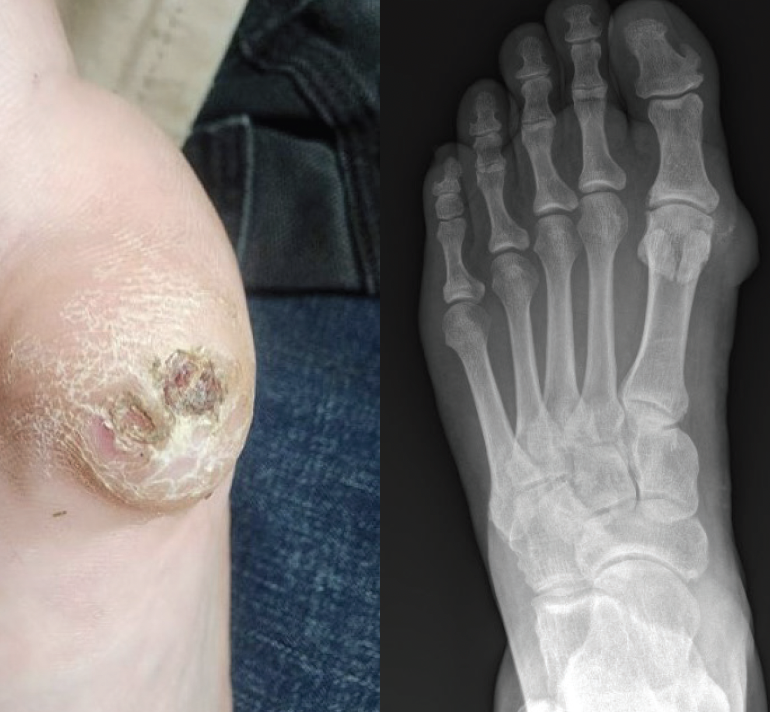

Upon initial examination, the mass appeared as a circular, thickened callus. The area was suspicious for an underlying ulcer due to visible serous drainage and what appeared to be dried heme trapped in the layers of hyperkeratosis. There were no observed irregularities in shape of the lesion or in the overlying skin color. The mass did not appear to interfere with the first MTPJ range of motion and was well defined, firm, and mobile on palpation (Figure 1). Initial plain film radiographs of the left foot showed soft tissue edema at the medial first metatarsal head extending to the MTPJ with some calcification in the soft tissue surrounding the first metatarsal head. There was no evidence of bone erosion or obvious osteophyte growth (Figure 2).